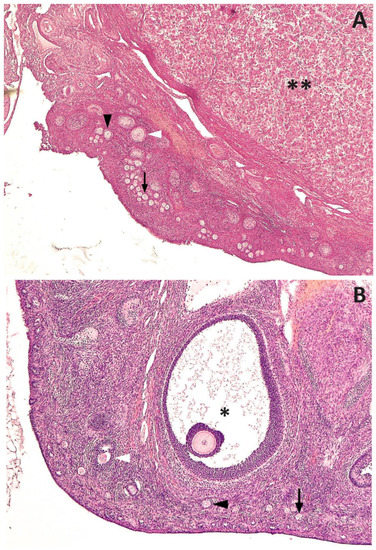

| Primordial | 80,931.08 ± 23,107.77 | 84.13 |

| Primary | 10,927.42 ± 2536.89 | 11.36 |

| Secondary | 7505.95 ± 3263.16 | 7.80 |

| Antral | 5.55 ± 5.55 | 0.01 |

| Total | 96,200.10 ± 26,125.12 |